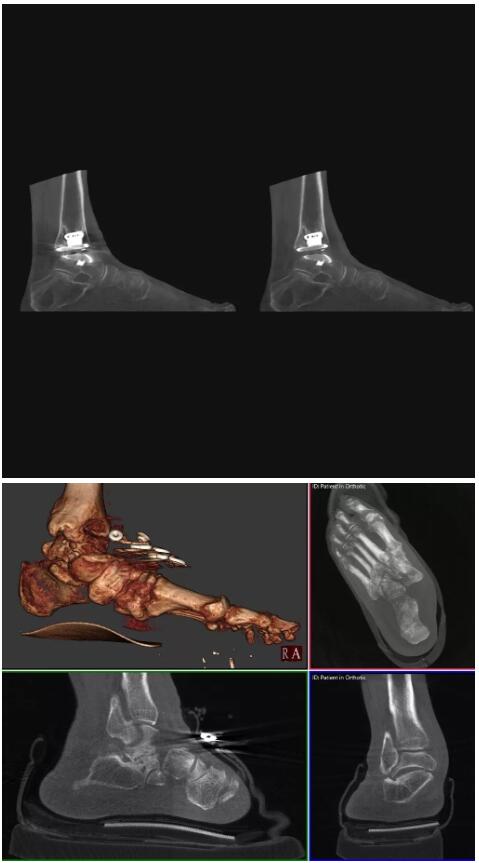

比如上面這款專用于足部和踝部掃查的CT成像系統(tǒng),患者在進行CT掃查時只需要站在上面即可,雙腳站或者單腳站都可以,當(dāng)然,如果患者不是那么方便站著做完CT掃查,也可坐在上面。

這款CT掃查系統(tǒng)自帶屏蔽裝置,它的體積非常小,僅需要極小的空間即可,并不像常規(guī)CT那樣需要一間單獨的檢查室。此外,這種CT掃查的速度非???,僅需30秒左右可以完成檢查,輻射劑量相對常規(guī)的CT要少許多,尤其適合醫(yī)院的骨科使用。

而患者站著做足部或者踝部做CT檢查還有個好處是,可以檢查患者在負重的情況下,骨關(guān)節(jié)的真實情況,而躺著做CT掃查時未必能看出來。負重CT掃查特別是對于受傷的運動員或者舞蹈員來說意義更大,能夠更準確地評估傷情,幫助他們盡早復(fù)原。

另外一款被稱為世界上最小的CT,它的重量僅300磅,不僅能夠掃查足部,還可以檢查膝蓋和上肢等。

與上面介紹的CT一樣,它同樣具有輻射低、占地空間小(23*36)的特點,隨開隨用(支持直接接入墻上的插座)。

這款CT使用非常方便,通過上下移動保持與患者的手臂或者雙腿齊平,掃描快速,僅需要30秒左右就可以完成掃查。

以上介紹的CT均來自國外同一家公司,這些CT均配置了可視化軟件,可以進行切片、3D重建以及大型CT附帶的所有典型的操作功能。

以下是這些“特立獨行”的CT所拍出來的圖像: